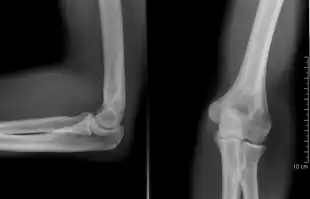

Left elbow extended and flexed

Normal radiograph; right picture of the straightened arm shows the carrying angle of the elbow

When the arm is extended, with the palm facing forward or up, the bones of the upper arm (humerus) and forearm (radius and ulna) are not perfectly aligned. The deviation from a straight line occurs in the direction of the thumb, and is referred to as the "carrying angle".[22]